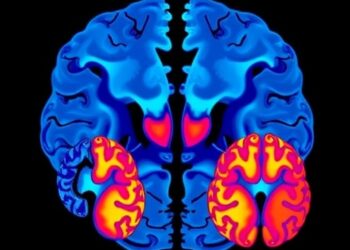

Brain Asymmetry in Parkinson’s: First vs. Body-First

In a groundbreaking advancement in the understanding of Parkinson’s disease (PD), recent research has unveiled distinct structural and functional asymmetries ...